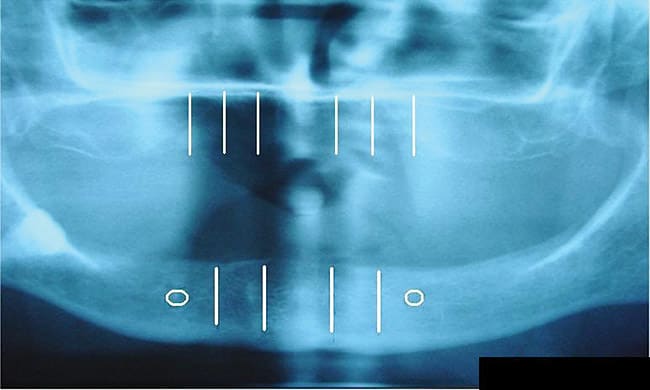

A panoramic roentgenogram or cone beam computed tomography scan was completed to assess bone parameters and plan implant placement sites. Consider the example of the stabilization of a maxillary and mandibular denture (Figure 1). The placement sites were marked on the radiograph between the canine and first bicuspid anterior to the mental foramen as well as in the region of lateral incisors anteriorly (Figure 2). Next, depending on the size and type of prosthesis, the quantity of mini implants to use was determined. The primary author recommends the placement of four mini implants for the stabilization of a full mandibular denture. While four mini implants may also be sufficient for a maxillary denture stabilization procedure, six are recommended if a palateless denture is being considered. For single tooth replacement one mini implant is used for anterior and bicuspid teeth, while for molars, often two mini implants are used.12,13 In this context, occlusal and masticatory forces are distributed over an augmented implant interface; the relative strain on any implant is reduced.13 Furthermore, the bridgework in these cases acts as a splint, anchoring adjacent implants and reducing micro-movement.13 Similarly, adjacent missing teeth replaced using mini dental implants should be splinted together.

The pilot hole for the mini implants was then made using a 1.2-mm pilot drill (approximately half the diameter of the mini implants). Using sterile surgical techniques17 the dentist drilled to the appropriate depth based on bone density evaluation and implant type selected. For very dense bone, a pilot hole was drilled to be 80% of the length of the implant. For moderately dense bone, the pilot hole depth was 60% of the length of the implant. For low-density bone (maxillary bone or soft mandibular spongy bone) the pilot hole was created at 50% the length of the mini implant. Because of the flapless surgical technique most often utilized with mini implants, a surgical stent (Figure 5) designed from preoperative dental models, x-rays, and/or cone beam CT scans provides for proper angulation in the bone. A pilot drill guide (Figure 6) was used to position the pilot hole in the center of the surgical stent sleeve and maintain correct trajectory of the drill.18,19 The pilot drill was used to puncture the tissue down to the bone, and after locating the bone surface the pilot hole was made with a tapping motion.